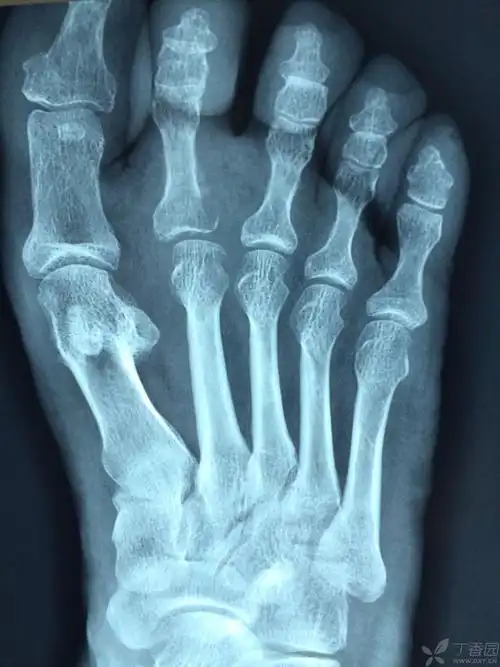

右足第二近节趾骨骨质破坏

右足第2近节趾骨骨皮质欠连续,余诸骨形态,结构未见异常,印象:考虑右

趾骨